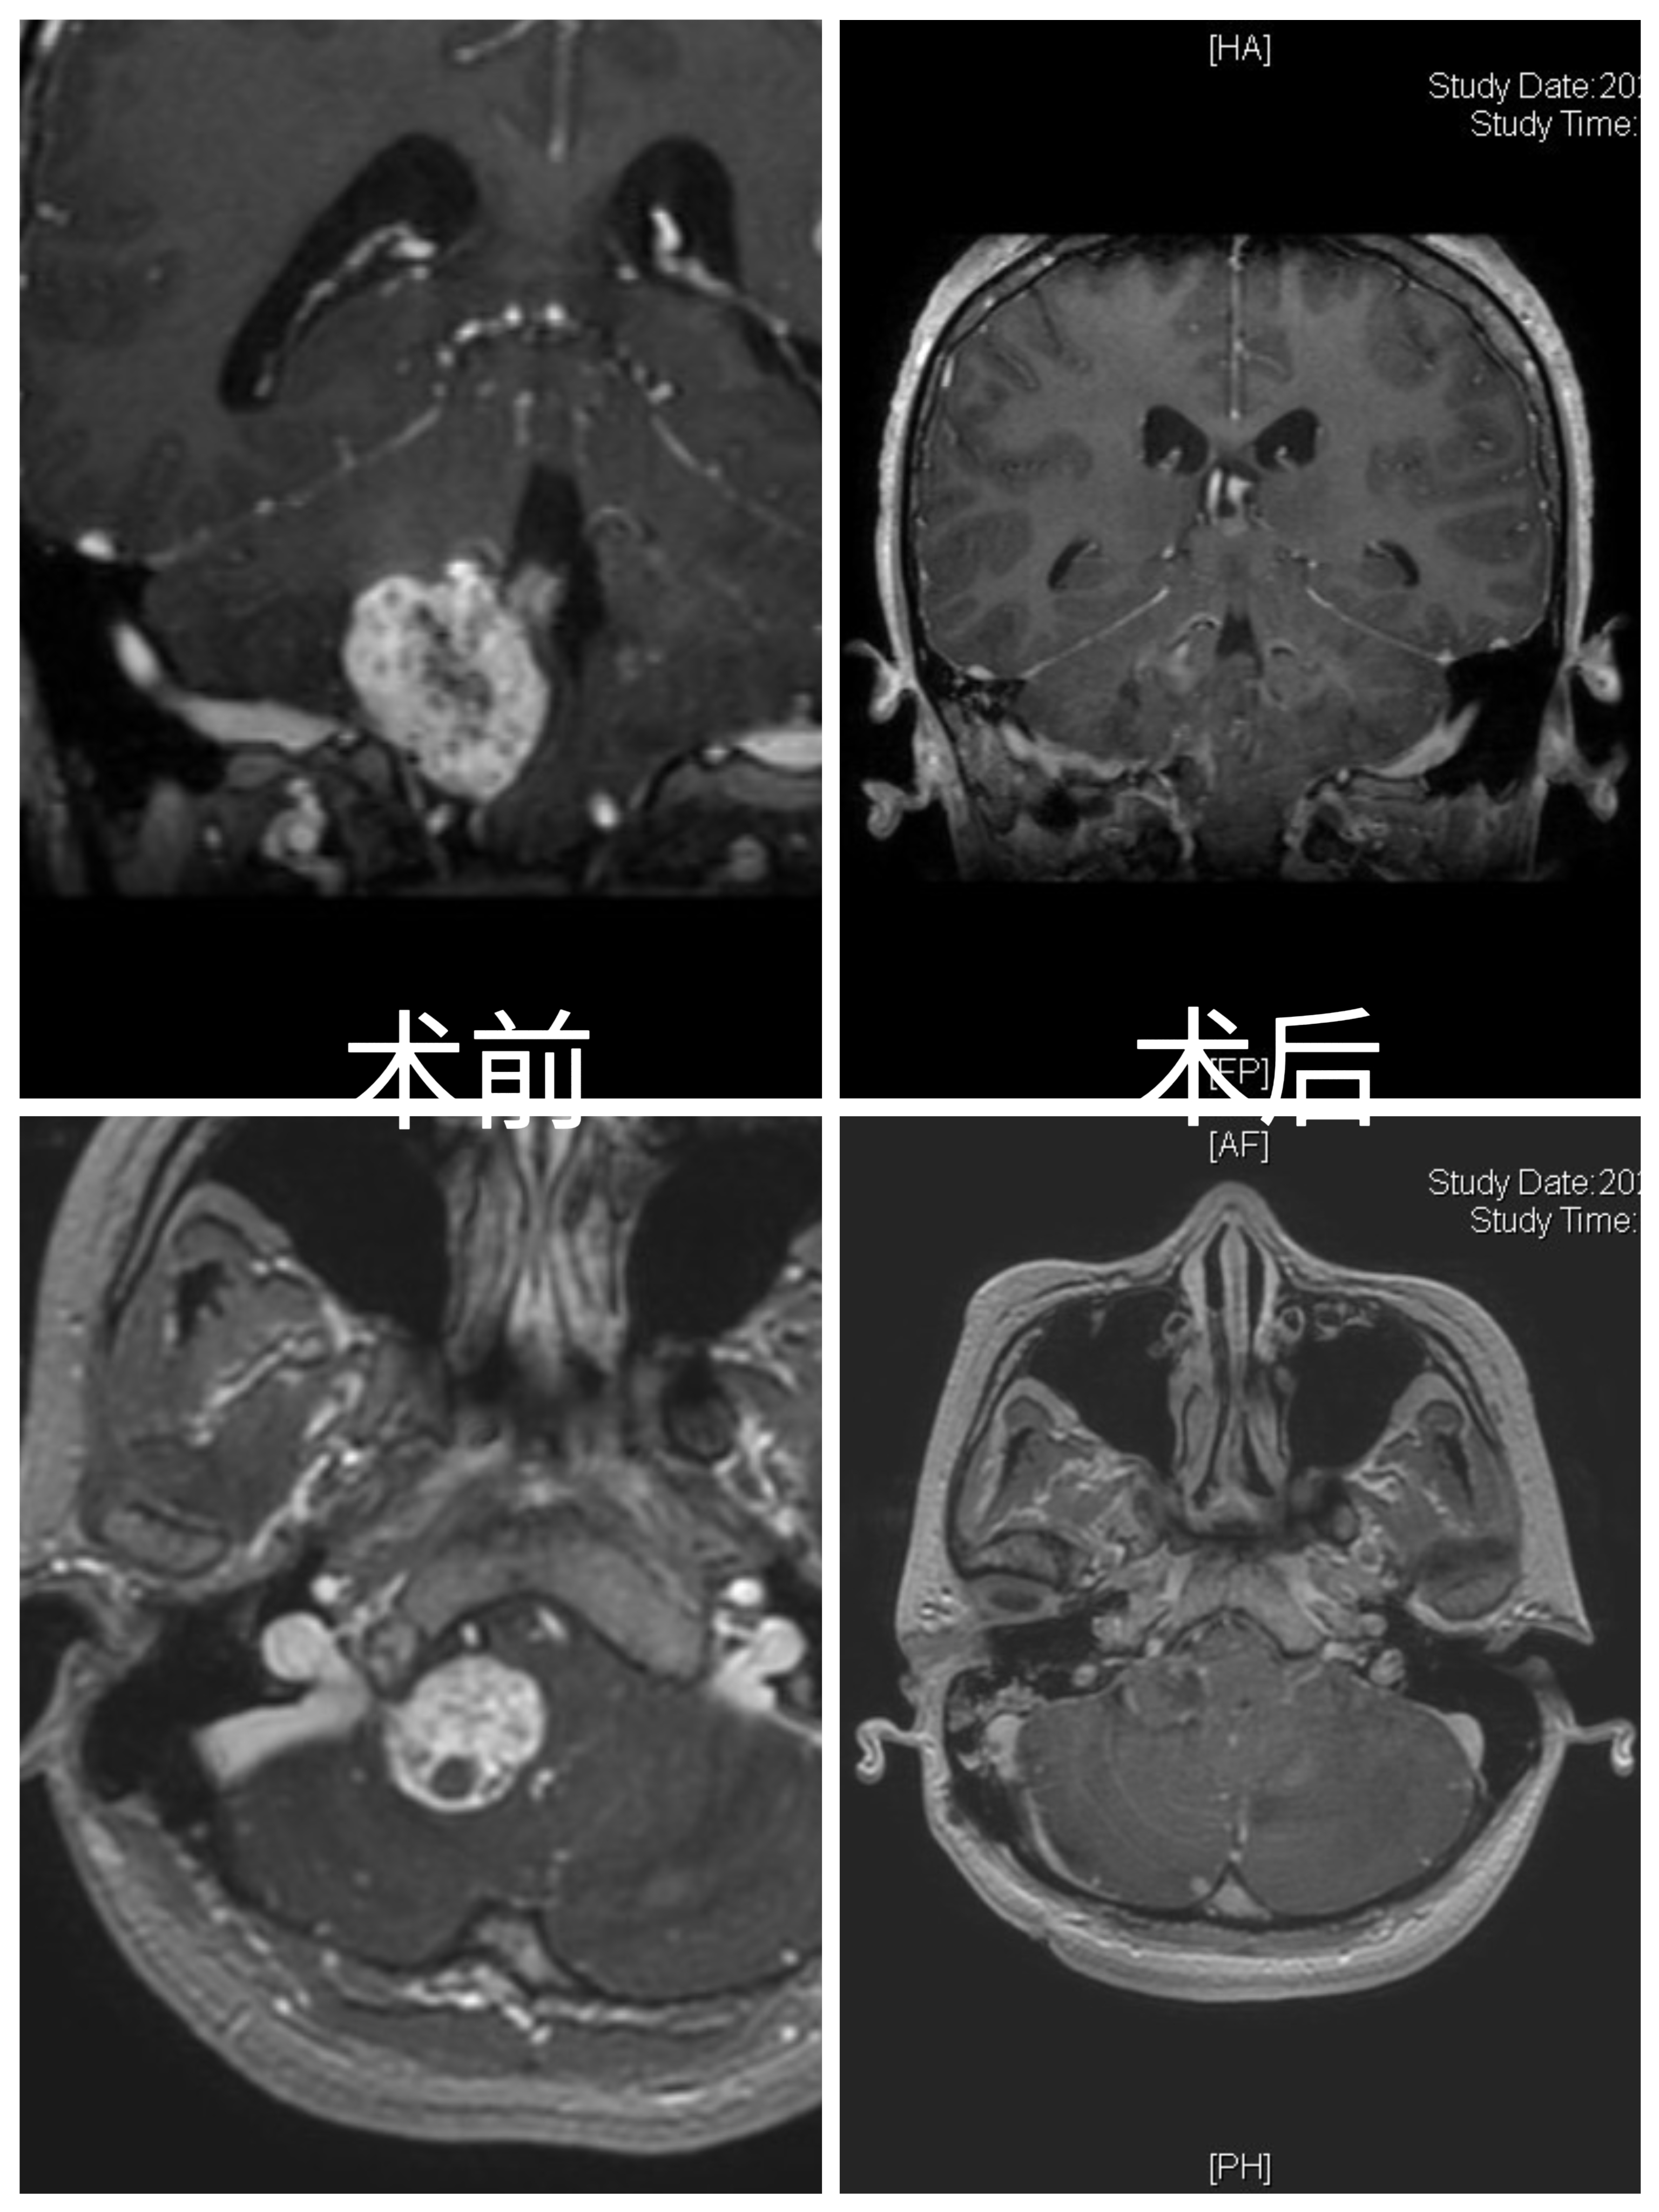

病例特点:

女性患者,26岁,因“间断性头晕1月余。”于2024-01-08入院。

患者1月余前感冒后出现头晕,伴头痛,伴恶心、呕吐。

家族史:患者母亲诊断多发小脑血管母细胞瘤,在我院手术治疗。

体检发现肝脏多发囊肿、右肾囊肿、胰腺多发囊肿。

诊断:延髓血管母细胞瘤

von Hippel-Lindau综合征